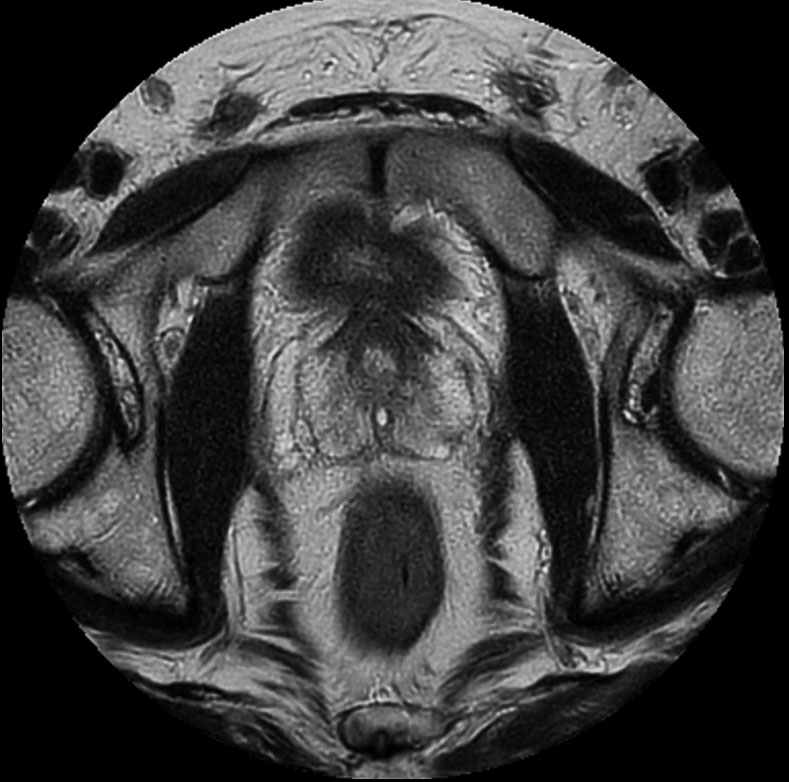

Prostate imaging

• Clinical Application